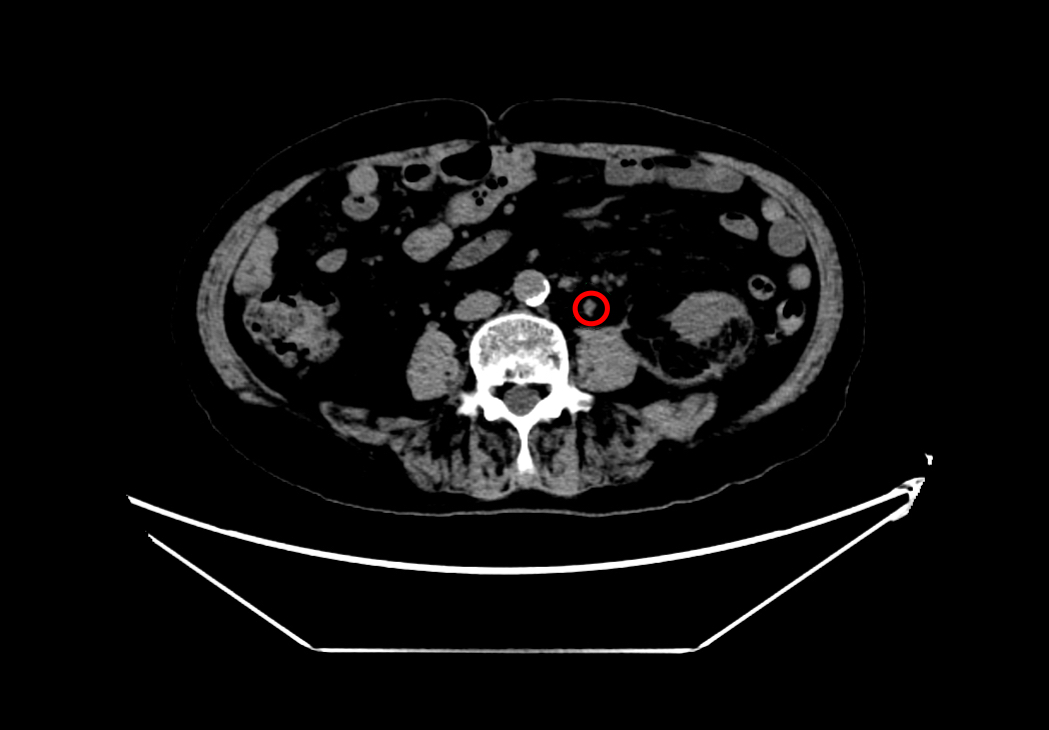

术前左肾结石

在魏武然主任医师和麻醉手术中心李晓强副主任医师的带领下,泌尿外科和麻醉科医疗团队对何爷爷进行了全面的术前评估,并针对可能出现的各类风险制定了周密的手术方案及应急预案。9月9日,手术如期进行。术中发现患者左肾中下盏存在多发结石,最大约2cm×1.5cm,质地坚硬,同时左输尿管上段见数枚不规则小结石,整体结石负荷大、分布复杂,进一步增加了手术难度。